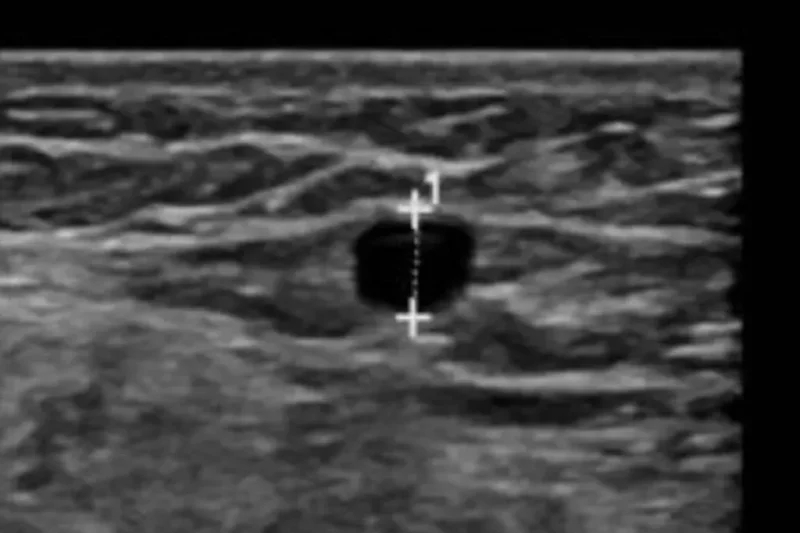

VenaSeal Ablation Q & A What is the VenaSeal™ System? The VenaSeal™ Procedure is an outpatient procedure using ultrasound and inserting a catheter into the diseased vein. The catheter …

Venogram Q & A What is a Venogram? Venography is as study that injects dye into a vein using a catheter that visualizes venous blood flow. As the dye …